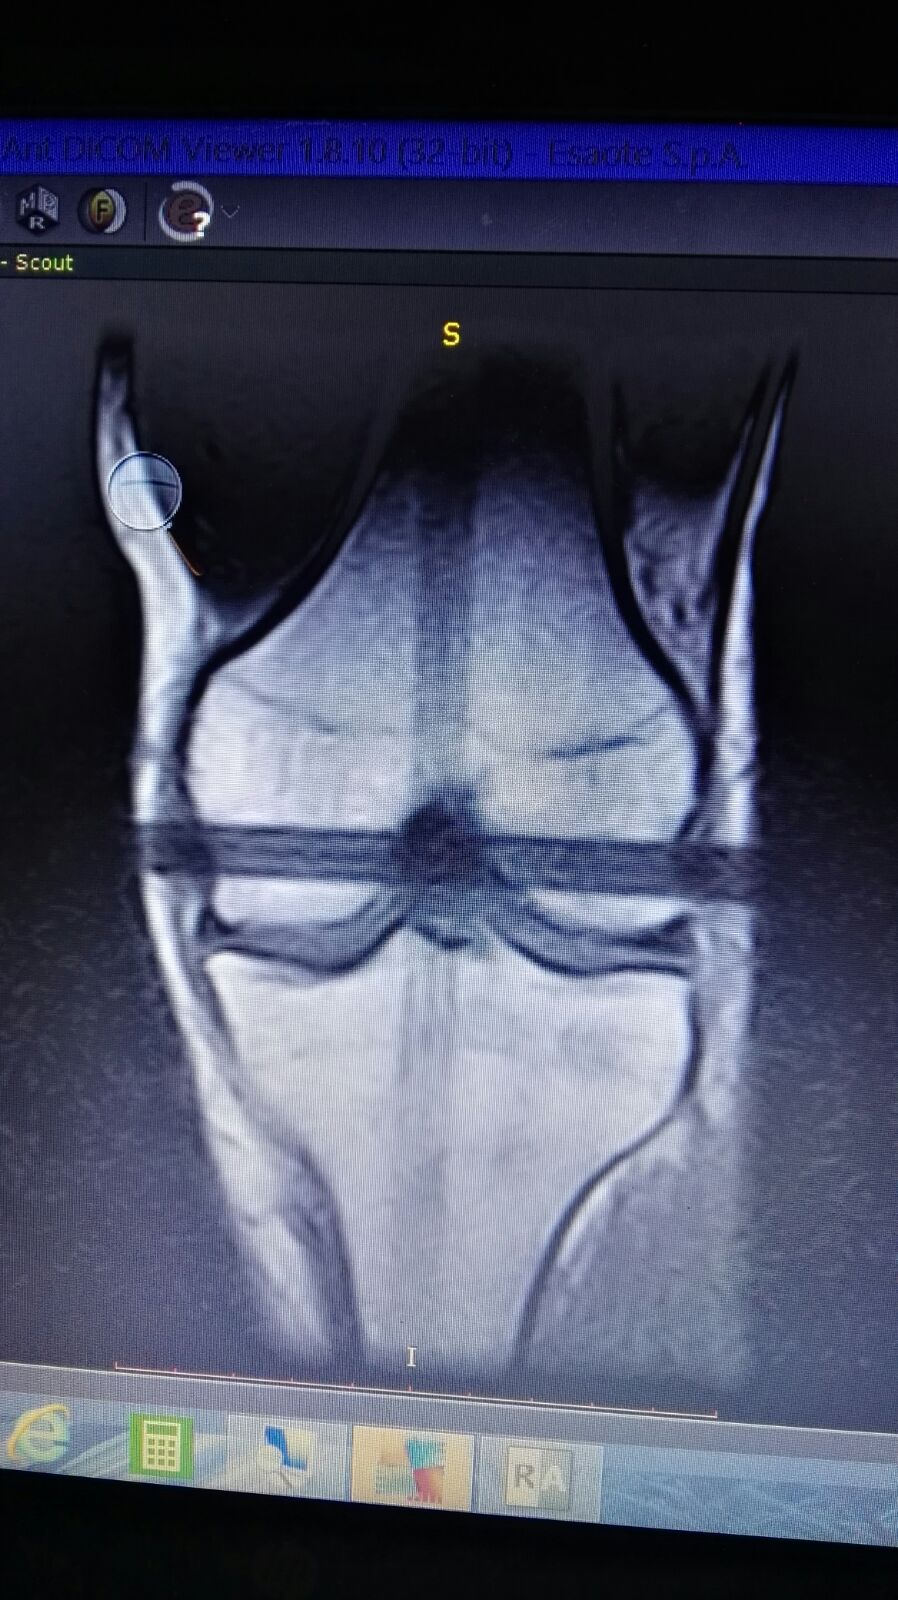

Salve mio marito circa un mese fa giocando a calcio si è fatto male il ginocchio. Essendo fuori per lavoro e riuscito solo a farsi una RSM LE mandi le foto se gentilmente può vederle. Lui è in addestramento per una missione volevo sapere se in un mese può farcela a guarire grazie mille.

IMG-20180301-WA0033.jpg

[ 205.56 KiB | Osservato 1320 volte ]